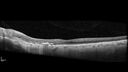

85 year old female: The patient notices that she needs glasses. She was told by an optometrist that her left eye was so bad she should have been born with glasses. She always had problems with the left eye. The vision did get better when she had cataract surgery. She did not need glasses as much. Lately, about once a month, especially in the dark, she sees a dot in the vision in the left eye (straight ahead). Medical Hx: Amblyopia OS. Chalazion upper lid OD. Dry eye OU. Meibomitis OU. Surgical Hx: Hysterectomy. Lumpectomy. Systemic Meds: metoprolol tartrate 50 MG (as metoprolol succinate 47.5 MG) Oral Tablet bid. Clonidine 0.1mg prn. Aspirin 81 mg. B12. D3. VA OD: Dsc20/40-2 VA OS: Dsc20/80 PH20/63 IOP: TP: OD:16 OS:16

Peripapillary CNVM No Treatment29 views85 year old with peripapillary CNVM watched for many years.00000